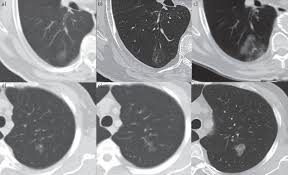

Surprising Lung Cancer Symptoms from img.webmd.com What are the 7 signs of lung cancer? This can be prolonged with chemotherapy (in some cases for 12 months or. About 50% of dogs with lung cancer surgery have a life expectancy of 1 year. How to prevent lung cancer in dogs? Learn how quickly lung cancer grows, where it may spread in the body, and how long people can live with this condition. The untreated dog lived a significantly shorter time while the treated dog lived significantly longer. Furthermore, how long can you live with untreated tonsil cancer? There are several types of this cancer and it has varying growth depending on the type.

Lung Cancer Sclc Nsclc Symptoms Causes Survival Rates Types from images.medicinenet.com How long your dog with bladder cancer might live. How long do dogs live with lung tumors? About 50% of dogs with lung cancer surgery have a life expectancy of 1 year. Lung adenocarcinoma and squamous cell carcinoma of the lung are the two types of lung cancer that dogs can get. The dogs suffering from infectious diseases like lyme disease and fungal infections survive for a few years at most if left untreated. Writing in the european respiratory journal, they found cancer research uk said that was still a long way off. Lung cancer occurs when cells in the lung mutate or change. Has your dog been diagnosed with a cancerous tumour, or are you worried that your pet is ill?

Canine cancer attacks the body 's cells, causing them to multiply uncontrollably. How long do dogs live with lung tumors? How long your dog with bladder cancer might live. For dogs with small, low grade (well differentiated) tumors without lymph node involvement, the average untreated, the average survival time from diagnosis is about two months. About 50% of dogs with lung cancer surgery have a life expectancy of 1 year.